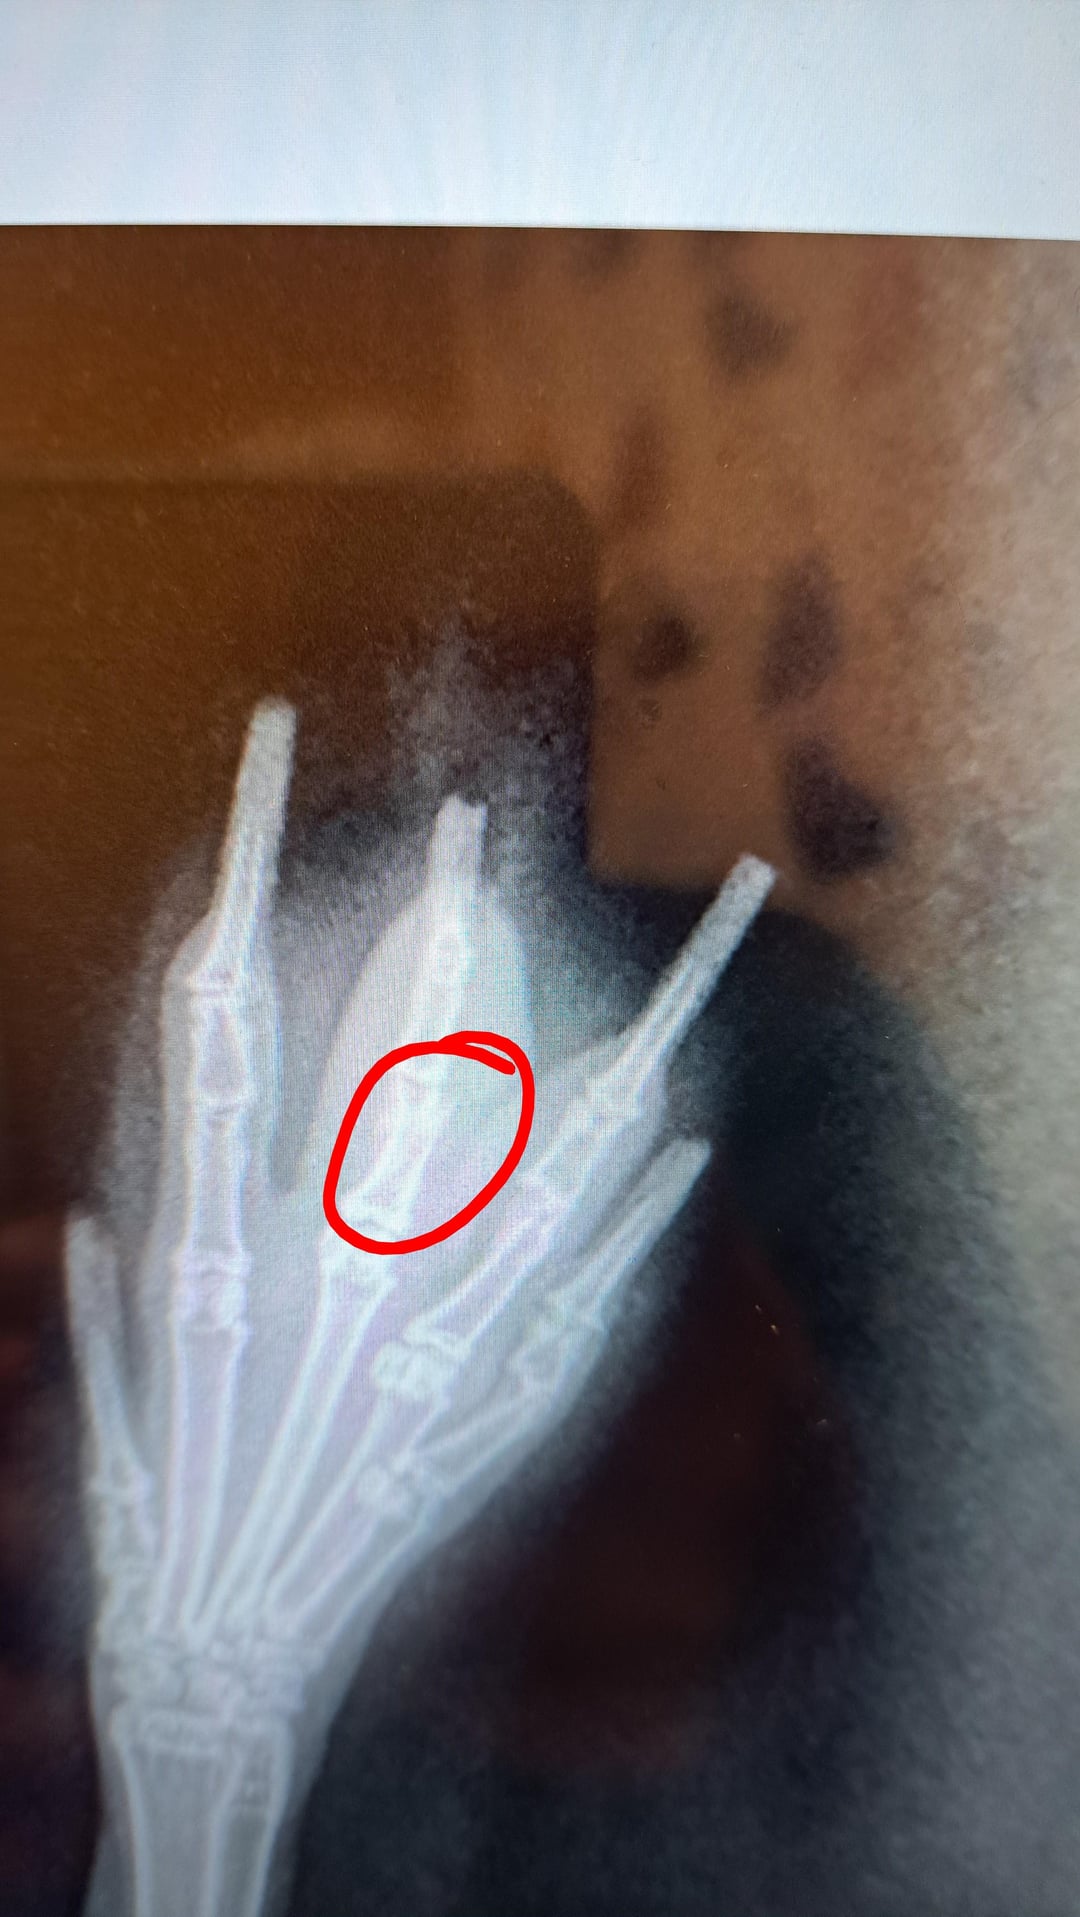

Got home from work today to find one of my girls favouring her front right paw. One (very expensive) trip to the emergency vet later and Pancake and I were back home with a broken toe diagnosis. I just can't get over how weird their feet look!!